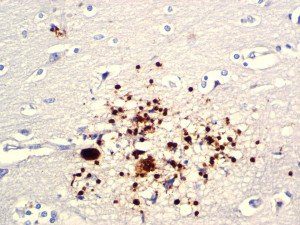

It is the ICU physician who is most likely to witness one of the deadliest manifestations of the abnormal immunological response, the cytokine storm syndrome (CSS). This response is also referred to by some as the cytokine release syndrome (CRS). CSS is characterized by continuous activation and expansion of macrophage and lymphocyte populations, which secrete large amounts of cytokines, causing the cytokine storm. This massive cytokine release is akin to hemophagocytic lymphohistiocytosis (HLH) disease, a syndrome characterized by initial unchecked and persistent activation of cytotoxic T lymphocytes and NK cells.

Clinical and laboratory manifestations of HLH include fever, enlarged liver and/or spleen, neurologic dysfunction, coagulopathy, liver dysfunction, cytopenias (i.e., low levels of erythrocytes, leukocytes, and/or platelets), hypertriglyceridemia, hyperferritinemia, hemophagocytosis, and eventually diminished NK cell activity as the immune system becomes progressively paralyzed. HLH can be familial (primary HLH) or secondary to another disease process (sHLH), such as rheumatic disease, in which it is referred to as macrophage activation syndrome (MAS, characterized by elevated ferritin).